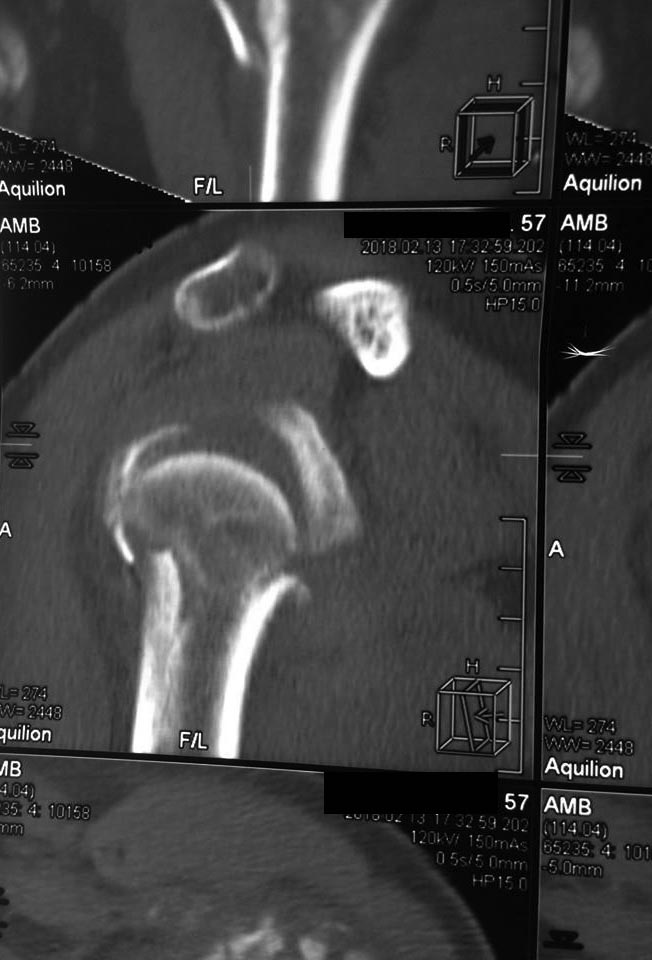

[Ortho] Перелом проксимального метаэпифиза плеча

Дорогие коллеги! Мнение о тактике лечения пациентки в нашем отделении

разделилось.

травма 10 дней назад, падение при катании на обычных лыжах. Сама

врач-рентгенолог 57 лет.

Левая рука, недоминатная. На данный момент ходит в косынке, вся в

сомнениях, что делать.

Мнения по лечению: - ничего не делать - остеосинтез пластиной

блокированной - первичное эндопротезирование (в наличие только геми,

delta не потянет) Может кто-то что более дельное предложит.